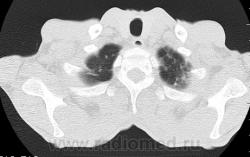

На фоне консолидации полость без содержимого. Может быть всё что угодно, что сопровождается деструкцией. Нужны ещё томограммы в лёгочном окне.

Изображения выставлены все. Ваше мнение уважаемые коллеги?

Туберкулёз.

Туберкулёз?

Это КТ 2-летней давности и попало оно мне в руки, после недавнего прохождения контроля пациентом, когда мы стали перед вопросом о специфическом / не специфическом процессе.

Тогда, пациента 2 месяца лечили от пневмонии, лечили интенсивности, стационарно, в серьёзном учреждении.

Предположу аспергиллез